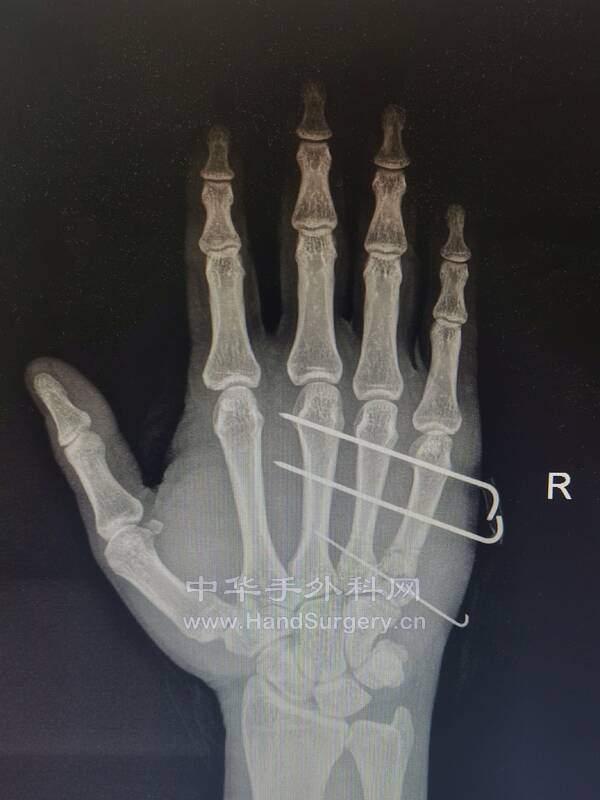

因为今天又做了一例

使用同样的方法

很快,微创,高效

今天的病例

这种关节内骨折的移位可能与Bennett骨折相似

因为尺侧腕伸肌腱的牵拉产生一种很大的使掌骨干向近端移位的趋势

与Bennett骨折中拇指掌骨的移位相似

这种骨折通常可以通过牵引复位,经皮穿针固定

对于哪些未能早期发现而在移位位置愈合的骨折,应通过愈合部位的截骨或关节切除成形术加以矫正

微信图片_20220614225637.jpg

微信图片_20220614225624.jpg